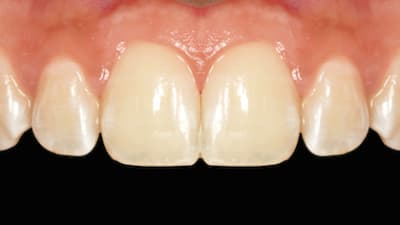

Online Only Periodontics Online Only Preservation of Natural Gingival Pigmentation When Treating Multiple Gingival Recession Defects By Douglas H. Mahn, DDS March 01, 2018 10 min read